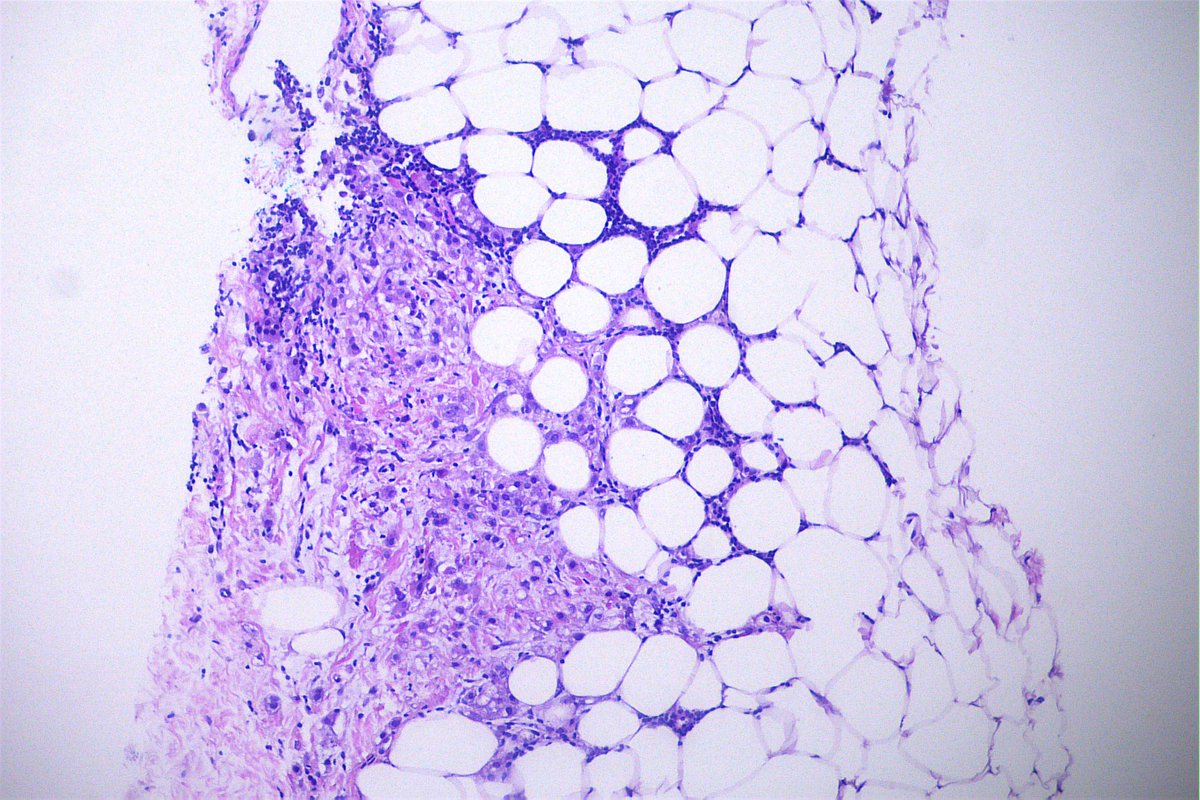

Case of the day. M, 30 years old, with weight loss, pulmonary consolidation area, mediastinal lymph node enlargement, and endobronchial polypoid lesions. Bronchial biopsy performed. #pulmpath #pathology